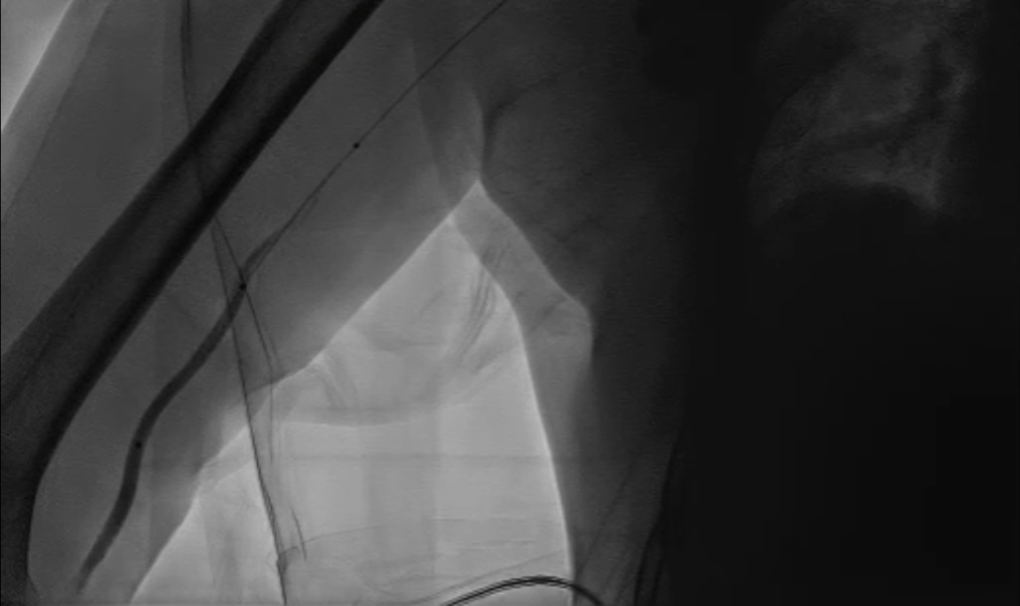

球囊扩张:采用同轴双导丝技术,以4×40mm、6×40mm球囊逐级扩张狭窄段;造影发现残存狭窄后,再次用6×40mm球囊扩张。

4*40mm球囊扩张

无名动脉支架

多角度造影

仍有残存狭窄

6*40mm球囊扩张

再次6*40mm球囊扩张